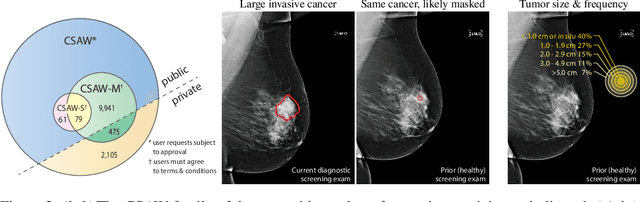

Abstract:Interval and large invasive breast cancers, which are associated with worse prognosis than other cancers, are usually detected at a late stage due to false negative assessments of screening mammograms. The missed screening-time detection is commonly caused by the tumor being obscured by its surrounding breast tissues, a phenomenon called masking. To study and benchmark mammographic masking of cancer, in this work we introduce CSAW-M, the largest public mammographic dataset, collected from over 10,000 individuals and annotated with potential masking. In contrast to the previous approaches which measure breast image density as a proxy, our dataset directly provides annotations of masking potential assessments from five specialists. We also trained deep learning models on CSAW-M to estimate the masking level and showed that the estimated masking is significantly more predictive of screening participants diagnosed with interval and large invasive cancers -- without being explicitly trained for these tasks -- than its breast density counterparts.